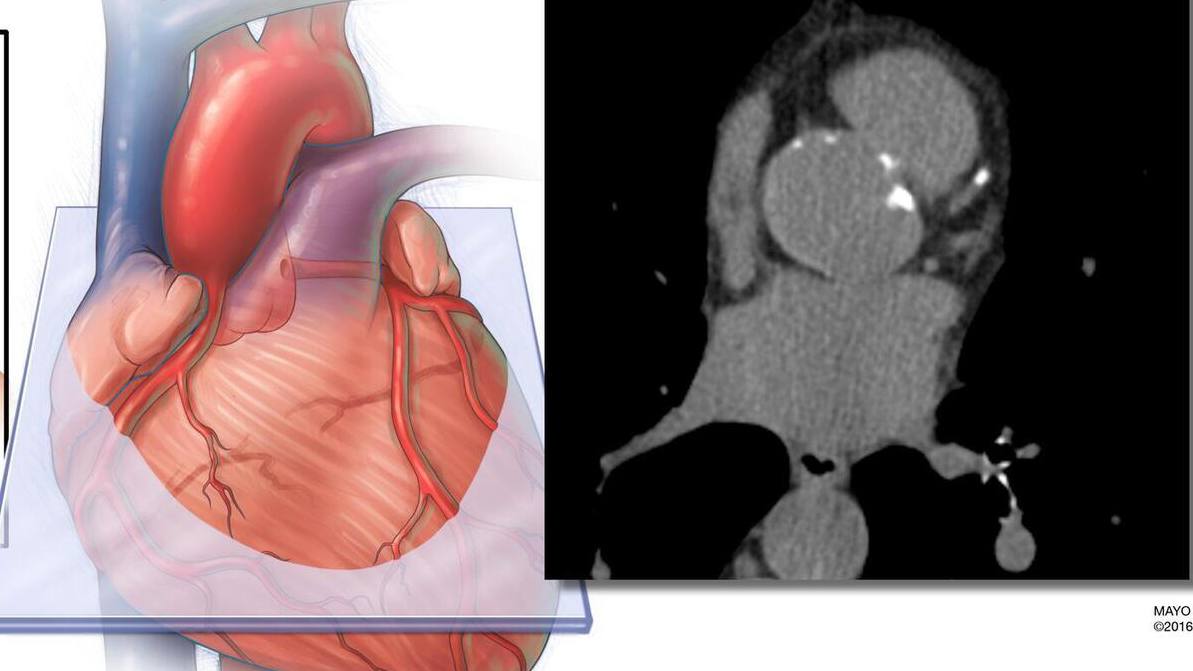

El estudio realizó un seguimiento de casi 12.000 adultos durante aproximadamente 16 años. Los investigadores aplicaron IA a las tomografías estándar de calcio en arterias coronarias de los participantes para medir la grasa que rodea el corazón. Compararon el valor predictivo de esta medición, tanto de forma independiente como en combinación, con dos enfoques estándar de evaluación del riesgo: la ecuación PREVENT de la American Heart Association, que incorpora factores tradicionales como edad, sexo, presión arterial, colesterol, diabetes y otras variables, y la puntuación de calcio en arterias coronarias, que cuantifica la placa calcificada en las arterias coronarias.

Los hallazgos muestran que el volumen de grasa cardíaca podría utilizarse de forma independiente para predecir eventos cardiovasculares. Además, mejoró de manera significativa la precisión global de la predicción del riesgo a largo plazo cuando se combinó con la puntuación de calcio coronario y la ecuación PREVENT, especialmente entre pacientes clasificados en categorías de bajo riesgo.

La cuantificación del calcio en arterias coronarias se utiliza ampliamente para evaluar el riesgo cardiovascular. Este estudio demuestra que puede extraerse información adicional de la misma exploración sin necesidad de pruebas adicionales ni costes añadidos.